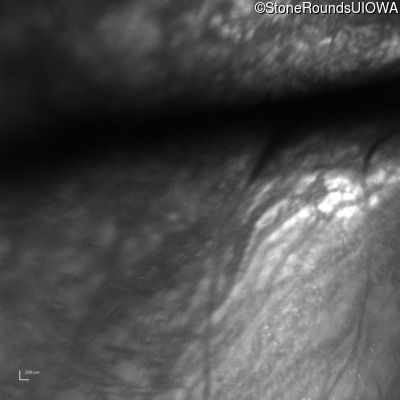

Optical Coherence Tomography - Right - 20/200 sc

Exemplar / OCT Stack